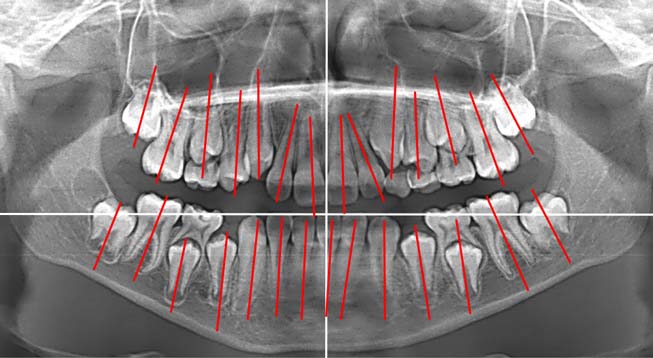

Кроме того, на ортопантомограмме выявили искривление корней постоянных зубов (рис. 7), что затрудняло их перемещение, а нормализация наклона корней при этом не представлялась возможной.

Рис. 7. Ортопантомограмма пациента Л. 15 лет

В результате ортодонтического лечения брекет-системой Damon Q с соответствующими силовыми элементами получен удовлетворительный результат (рис. 8).

Рис. 8. Диагностические модели челюстей пациента Л. 17 лет: А — вид справа; Б — модель верхней челюсти; В — модель нижней челюсти; Г — вид слева

На ортопантомограмме после завершения ортодонтической коррекции окклюзии выявлены незначительная асимметрия положения зубов и искривление корней отдельных зубов (рис. 9).

Рис. 9. Ортопантомограмма пациента Л. 17 лет

Положение зачатков зубов 2.8, 3.8 и 4.8 в динамике наблюдения от 15 до 17 лет ухудшилось (рис. 10).

Рис. 10. Изменение наклона нижних третьих постоянных моляров пациента Л. относительно окклюзионной плоскости на ортопантомограммах в возрасте 15–17 лет

Это подтверждала динамика наклона осей постоянных зубов и зачатков третьих постоянных моляров относительно окклюзионной плоскости (табл. 3).